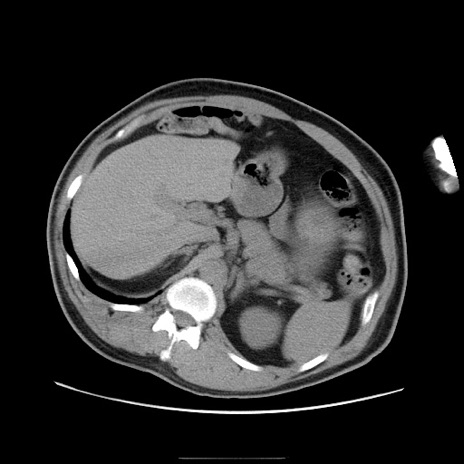

症例

冠状断像